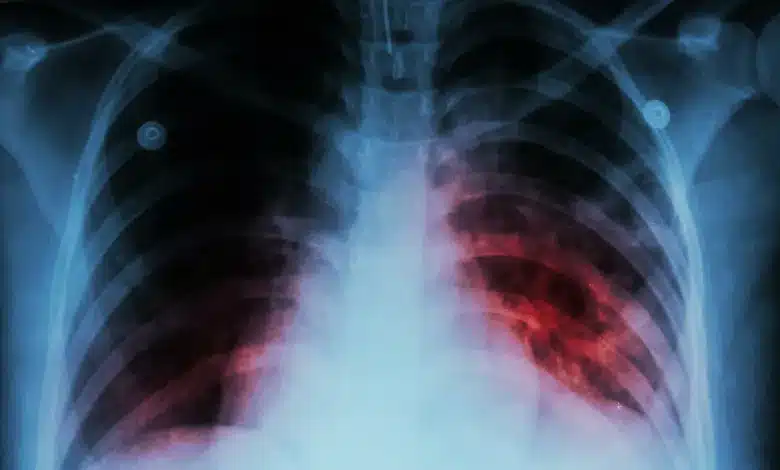

Tuberculosis, an infectious disease primarily affecting the lungs, is a bacterial infection transmitted through the air. Symptoms include prolonged cough, chest pain, weakness, fatigue, weight loss, fever, and night sweats.